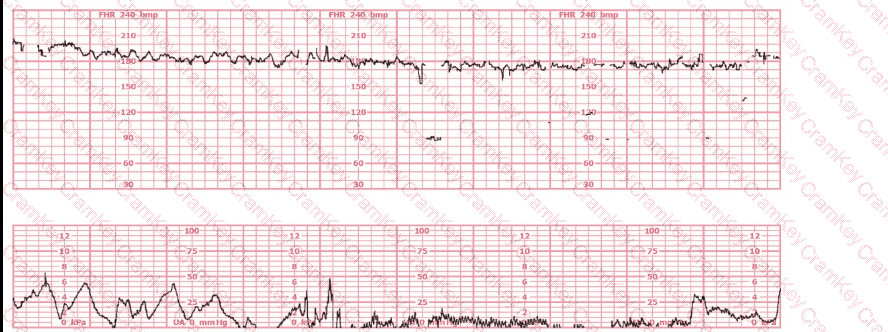

A 30-year-old woman (G2P0) is experiencing preterm labor at 26-weeks gestation. She is receiving magnesium sulfate for neuroprotection. Her external fetal monitoring tracing over the past 30 minutes is shown. The next step would be to:

What is the appropriate interpretation of this tracing?